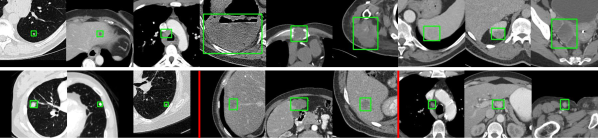

Refer to caption

Figure 2: Exemplar lesions from DeepLesion (first row), LUNA (second row 1–3), LiTS (4–6), and NIH-LN (7–9). DeepLesion has an overlap with the single-type datasets (first row 1–3), but it also includes many clinically significant lesion types that are not covered by other datasets (first row 4–9), demonstrating the value a ULD system.